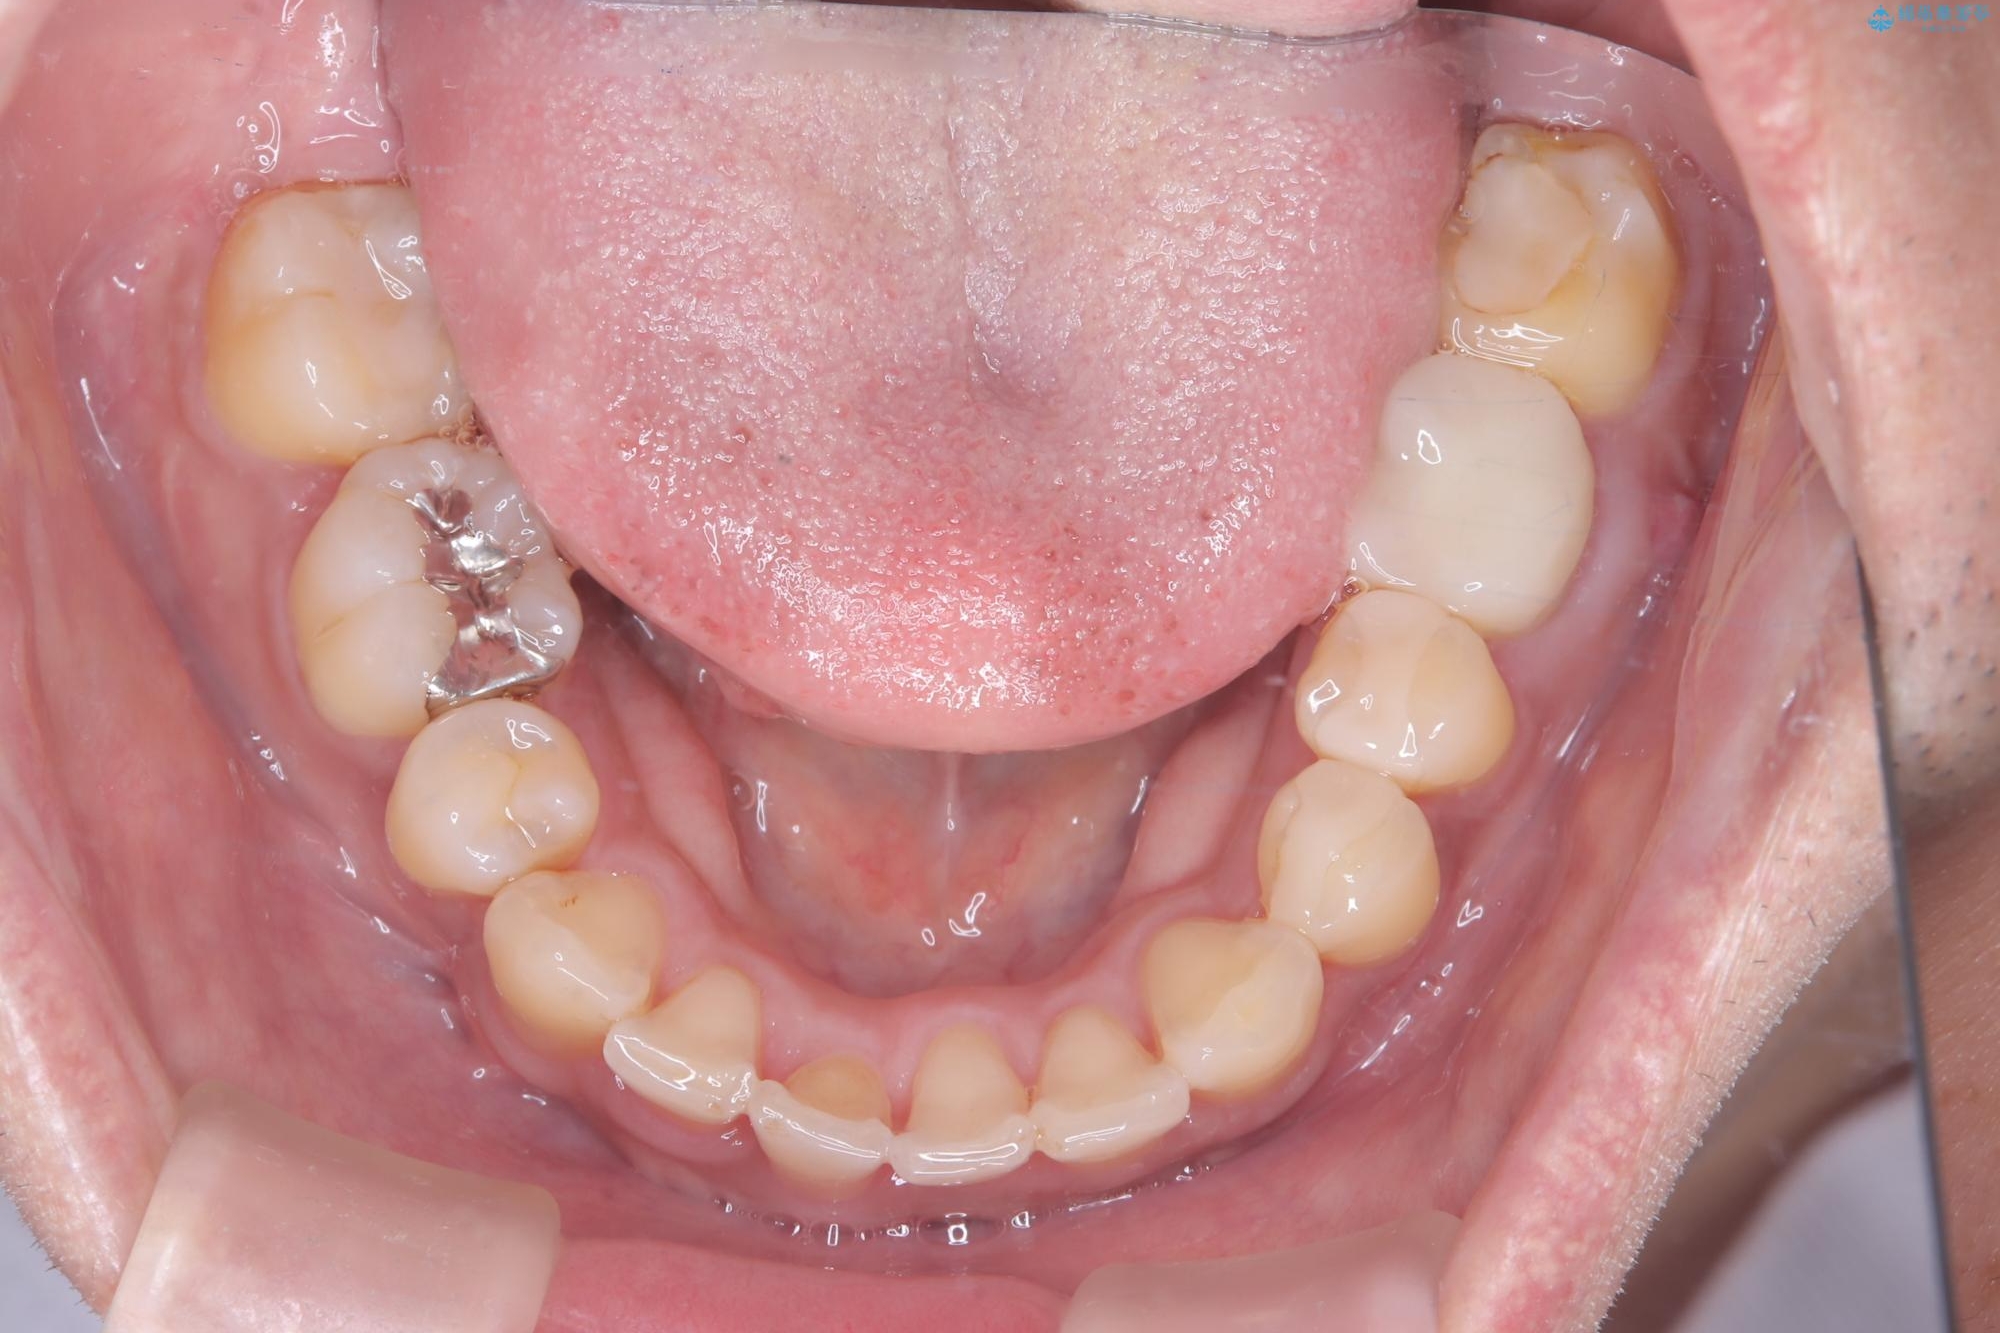

【ワイヤー矯正】八重歯と下の歯の凸凹を治したい

- 主訴:右上の八重歯と、下の歯の凸凹を治したい

上顎右側第一小臼歯と下顎右側第一小臼歯を抜歯しワイヤー矯正を行いました。

右側2級、左側1関係だったため、右側上下第一小臼歯を抜歯し、ワイヤー矯正を行いました。